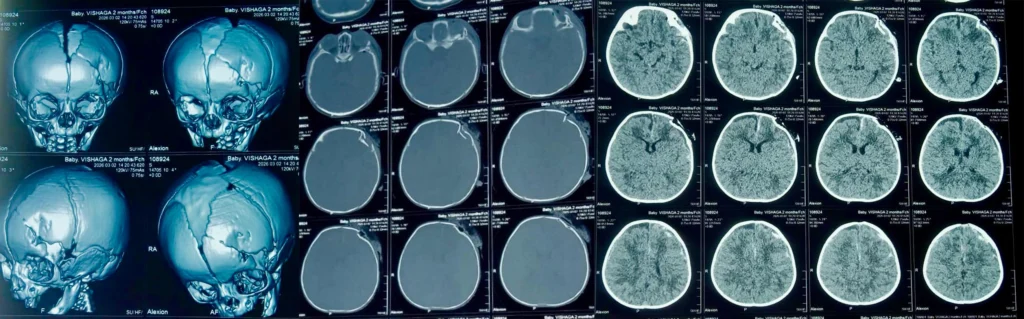

CT Brain Findings

Imaging revealed multiple serious injuries:

Depressed frontal skull fracture with bone fragments impinging on the frontal lobe

Subdural hemorrhage

Subarachnoid hemorrhage with perilesional edema

Parietal bone fracture

Hemotympanum

Pneumocephalus

Fracture extending to the superior orbital wall with air pockets

These findings confirmed severe head trauma requiring emergency neurosurgical intervention.